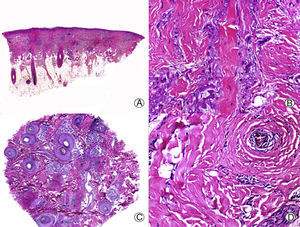

From an histopathologic point of view, PB is characterized by the absence of interface dermatitis, unlike LPP or CCLE, but distinctive histopathologic features of PB have not been reported.33 Early lesions present scant or moderate perifollicular lymphocytic infiltrate, which predominates in the periinfundibular region.29 Sebaceous glands are destroyed early in the process.34 As the condition progresses, lamellar fibroplasia appears around the follicular infundibula, leading to complete destruction of the pilosebaceous unit, with the appearance of fibrous tracts in its place (Fig. 3). The arrector pili muscle remains intact and foreign body granulomas can be observed around the hair shafts.29 In PB, staining for elastic fibers shows these structures to be notably thickened both in the adventitial and reticular dermis,11 an observation that assists in the differential diagnosis with other PCAs in advanced phases.

Longstanding pseudopelade of Brocq. A, Low-magnification view showing columns of fibrosis replacing the follicles (hematoxylin and eosin [HE] x10). B, Detail of the previous image showing vertical fibrosis mixed with actinic elastosis (HE x200). C, Transversal section of the same case, showing several follicular units (HE, X20). D, At higher magnification, concentric fibrosis around follicular remnants can be observed (HE x200).